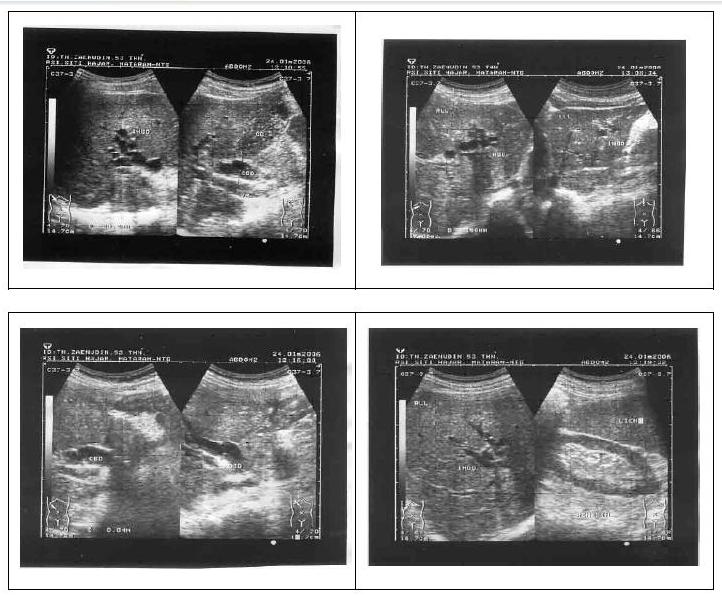

Hasil USG abdomen tanggal 12 Januari 2006 didapatkan Hepar : ukuran normal, intensitas echoprenkim homogen normal, tepi rata, sudut tajam, tak tampak pelebaran IHBD/EHBD, v. Hepatika/v.Porta tampak normal, tak tampak nodul/kista. Gall bladder : ukuran normal, dinding tidak menebal, duktus cystikus tampak normal, tak tampak pelebaran common bile duct. Pankreas/Lien : ukuran normal, intensitas echoparenkim homogen normal, tidak tampak nodul/kista. Ren D/S : ukuran normal, ukuran echocorteks homogen normal, batas sinus cortex jelas, tak tampak batu/nodul/kista. Kesimpulan : tidak tampak gambaran obstruksi common bileduct. Hasil USG disimpulkan adanya kolestasis intrahepatik yang belum diketahui penyebabnya maka kemudian dilakukan pemeriksaan PCR untuk mendeteksi virus Hepatitis E dan didapatkan hasil PCR Hepatitis E negatif. Pemeriksaan imunoserologi IgM anti HAV hasilnya negatif.

Karena hasil Patologi anatomi dari biopsi hati menunjukkan adanya kolestatik ekstrahepatik, maka dilakukan pemeriksaan USG abdomen ulang pada tanggal 24 Januari 2006 dan didapatkan Hepar : ukuran membesar ringan, permukaan rata, tepi tajam, echoparenkim baik, tak tampak nodul/abses. IHBD/CBD dilatasi sampai distal, tak tampak batu. Gall bladder tampak penuh dengan sludge. Pancreas kesan normal. Lien normal. Ren

D/S normal tak tampak batu/ectasis. Kesimpulan Ikterus obstruktif ekstra hepatik dengan sludge pada gall bladder.